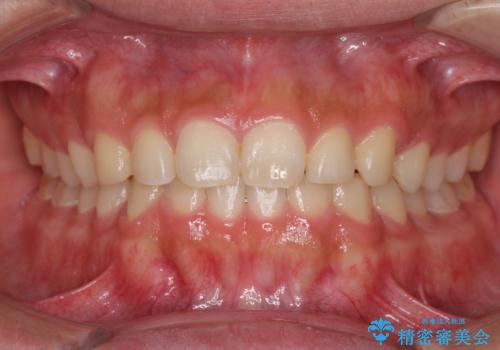

インビザラインによる、すきっ歯の改善

- 前歯がすきっ歯であることを気にして来院された患者様です。

下の前歯がほとんど隠れてしまうくらいの深い咬み合わせであったので、インビザラインを用いて、咬み合わせの高さを改善しながら隙間を閉じていくこととしました。

咬合力で上の前歯が前方に押し出されるようにして隙間ができていましたが、矯正治療により全て閉じることができました。

深い咬み合わせも多少改善され、隙間も閉じたことで、前方に出ていた前歯が引っ込んだため、口も閉じやすくなったとのことでした。